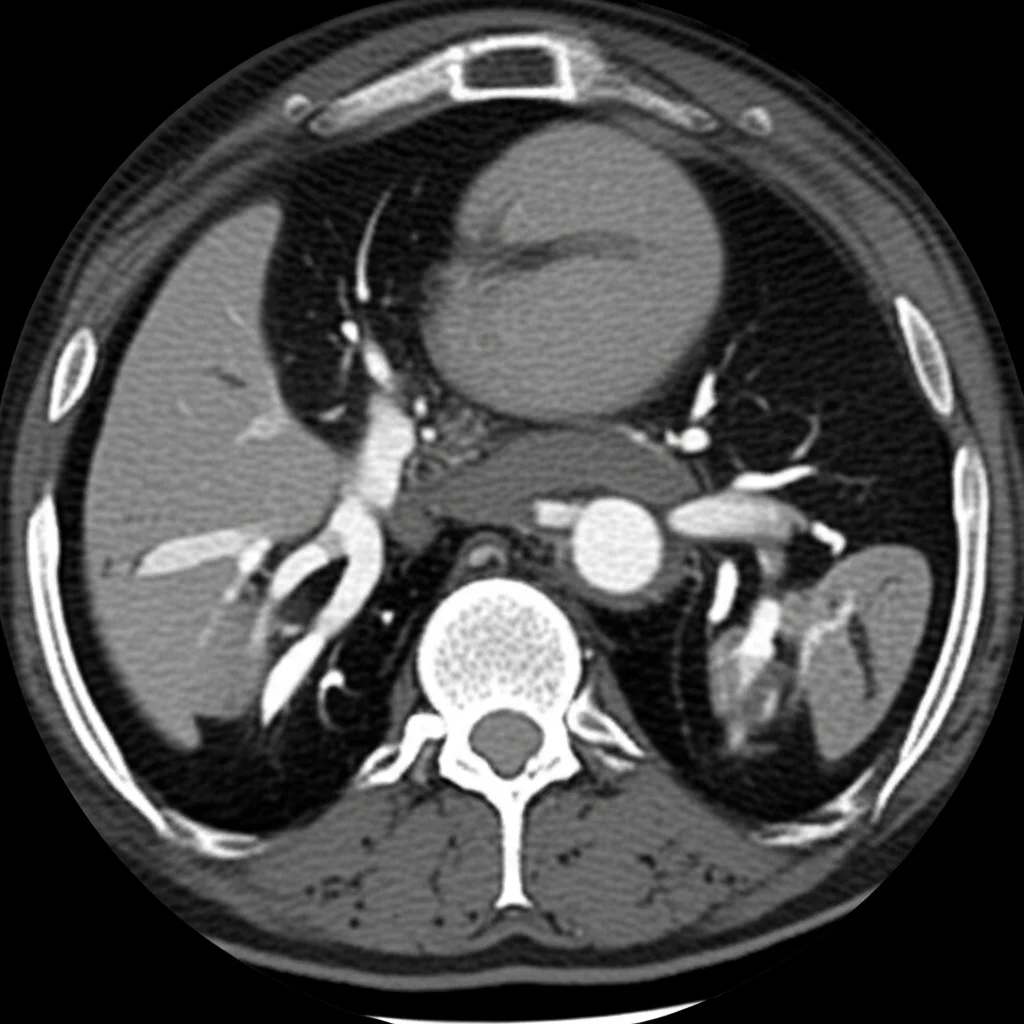

Ma la vera forza sta nell’unione! Lo studio ha combinato la NMRTD con una scansione standard di risonanza magnetica dell’addome e della pelvi (RM addomino-pelvica). E qui le scoperte si sono moltiplicate!

Mentre la DLG mostrava principalmente il flusso (o il non-flusso) del contrasto, la RM addomino-pelvica ha rivelato un quadro molto più completo delle anomalie presenti in queste pazienti:

- Dilatazione e tortuosità dei vasi linfatici nel retroperitoneo e nella pelvi (viste nel 100% dei casi, confermando i dati DLG ma con maggior dettaglio anatomico).

- Coinvolgimento di utero e vagina in quasi la metà dei casi (44.4%).

- Presenza di linfangiomi multipli (piccole cisti linfatiche) in sedi inaspettate: nella milza (44.4%), nel tessuto sottocutaneo (38.9%), nelle ossa (33.3%) e nelle labbra vaginali (16.7%). Queste sono cose che la DLG semplicemente non può vedere!

- Linfoedema perineale (gonfiore nella zona tra ano e genitali) nel 100% delle pazienti, visualizzato chiaramente dalla RM come un ispessimento dei tessuti con un tipico segnale “a griglia”.

- Presenza di versamento addomino-pelvico (liquido libero) in oltre la metà dei casi (55.6%).

- In un caso, la RM ha mostrato una grossa massa vulvare con vasi linfatici “nutrienti” che la raggiungevano, informazioni cruciali per pianificare l’intervento chirurgico.

Quindi, capite? La NMRTD ci dà una mappa dettagliata e non invasiva del “tubo” principale, il dotto toracico, mentre la RM addomino-pelvica ci mostra tutto il contesto, le conseguenze del malfunzionamento linfatico e altre anomalie sistemiche associate, spesso legate a quelle che vengono chiamate Anomalie Linfatiche Generalizzate (GLA), presenti nella stragrande maggioranza (94.4%) delle pazienti dello studio.